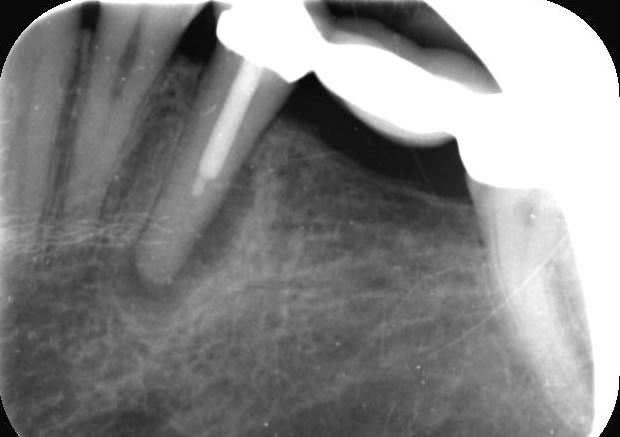

Circa 25 jaar geleden heb ik een brug laten plaatsen omdat een kies getrokken was. Nu recent bij de tandarts geweest en die gaf aan dat er op een foto een kleine ontsteking waarneembaar is onder de 1ste pijler van de brug. Het betreft element 35. 25 jaar geleden is er in dat element een wortelkanaalbehandeling uitgevoerd maar die is schijnbaar niet diep genoeg geweest?? Ook "lekt" de brug op dat element. Er is een breuk langs de wortel ontstaan. Ik heb nu compleet GEEN last maar e.e.a. is wellicht een tikkende tijdbom. Al bij een specialist geweest maar die gaf al heel snel aan trekken van element, twee implantaten met kronen, etc... Dat wordt een duur grapje en vraag nu me oprecht af of het nodig is. Nieuwe brug snap ik want die is end of life maar kan de wortelkanaalbehandeling niet opnieuw en/of kan men die breuk niet dichten? Dan gaat die ontsteking toch ook weg? Het lijkt allemaal wat rigoreus nu. Wil eigenlijk e.e.a. gewoon behouden maar lijkt of men daar geen inspanning voor wil doen. Graag advies.

Mogelijk een breuk maar dat kan ik op deze foto niet zien. Zo ook niet een lekkage in de 35 op deze foto te zien , wellicht bij onderzoek in de mond wel te voelen. Ik zie eerder een lekkage bij de achterste pijler 37 die ik zou onderzoeken. Is de specialist waar u geweest bent een endodontoloog?. Ik bedoel niet een tandarts met affiniteit endodontie. Op de foto lijkt een herbehandeling v d 35 mogelijk. Moet wel onderzoeken wat men bedoelt met een breuk langs de wortel. Maar een breuk dichten, denk het niet.

Dank voor de snelle reactie. Ik ben inderdaad bij een endodontoloog geweest maar zat daar welgeteld nog geen 10 minuten. Ik gaf aan dat de brug ruim 20 jaar oud was en na het maken van de foto was eigenlijk direct al de conclusie dat ie eruit moest. Ik heb ze overigens nogmaals benaderd omdat ik ook zelf vind dat ik geen duidelijke uitleg heb gehad. Kwam allemaal wat gehaast over en voornaamste reden zou zijn dat het element waar die wortelkanaalbehandeling op is uitgevoerd langs de wortel zou lekken waardoor de ontsteking is ontstaan. Nogmaals die ontsteking voel ik niet maar moet op uitspraak van de tandarts en de endodontoloog vertrouwen dat ie er zit. Moet daar ook niet mee blijven rondlopen maar vind de huidige conclusies wel erg snel getrokken. Bijgaand nog een foto want ik heb vorige week alles doorgestuurd gekregen van mijn eigen tandarts. Desnoods wil ik graag elders een second opinion. Tandarts kijkt ook alleen naar verslag/behandeladvies van de endodontoloog. Wat moet gebeuren dat moet gebeuren maar wil voorkomen dat onnodig of uit gemakzucht een element wordt getrokken terwijl ie wellicht nog prima te redden is. Heb ook totaal geen klachten nu

Tandarts_Richa…

Dat de ontsteking er is..is duidelijk. Ik ga op het advies v d endodontoloog af. Maar dat komt omdat, dorr ervaring met hem, geleerd heb dat hijeigenlijk altijd gelijk heeft. U kunt altijd een second opinion inwinnen bij een ander endodontoloog. Maar als de conclusie is, dat de 35 niet te redden is, moet het duidelijk zijn. Voor een vaste oplossing zou ik ook voor twee implantaten opteren. Dit omdat de 44 gaaf lijkt en het zonde zou zijn het te beslijpen als pijler element voor een brug 44-47.(gemiddeld 4x 800 eur.). Wel goedkoper dan twee implantaten (gemiddeld 4000 eur.). Maar voordeel v e brug zou, los v nadeel 44, dat de 47 gelijk een nieuw kroon heeft. Dus misschien toch de beste optie. Anders als uitneembare voorziening een frame prothese. Alles afhankelijk v d rest v h gebit. Geen klachten is geen reden het uit te stellen. Zou dat nooit doen in uw geval.